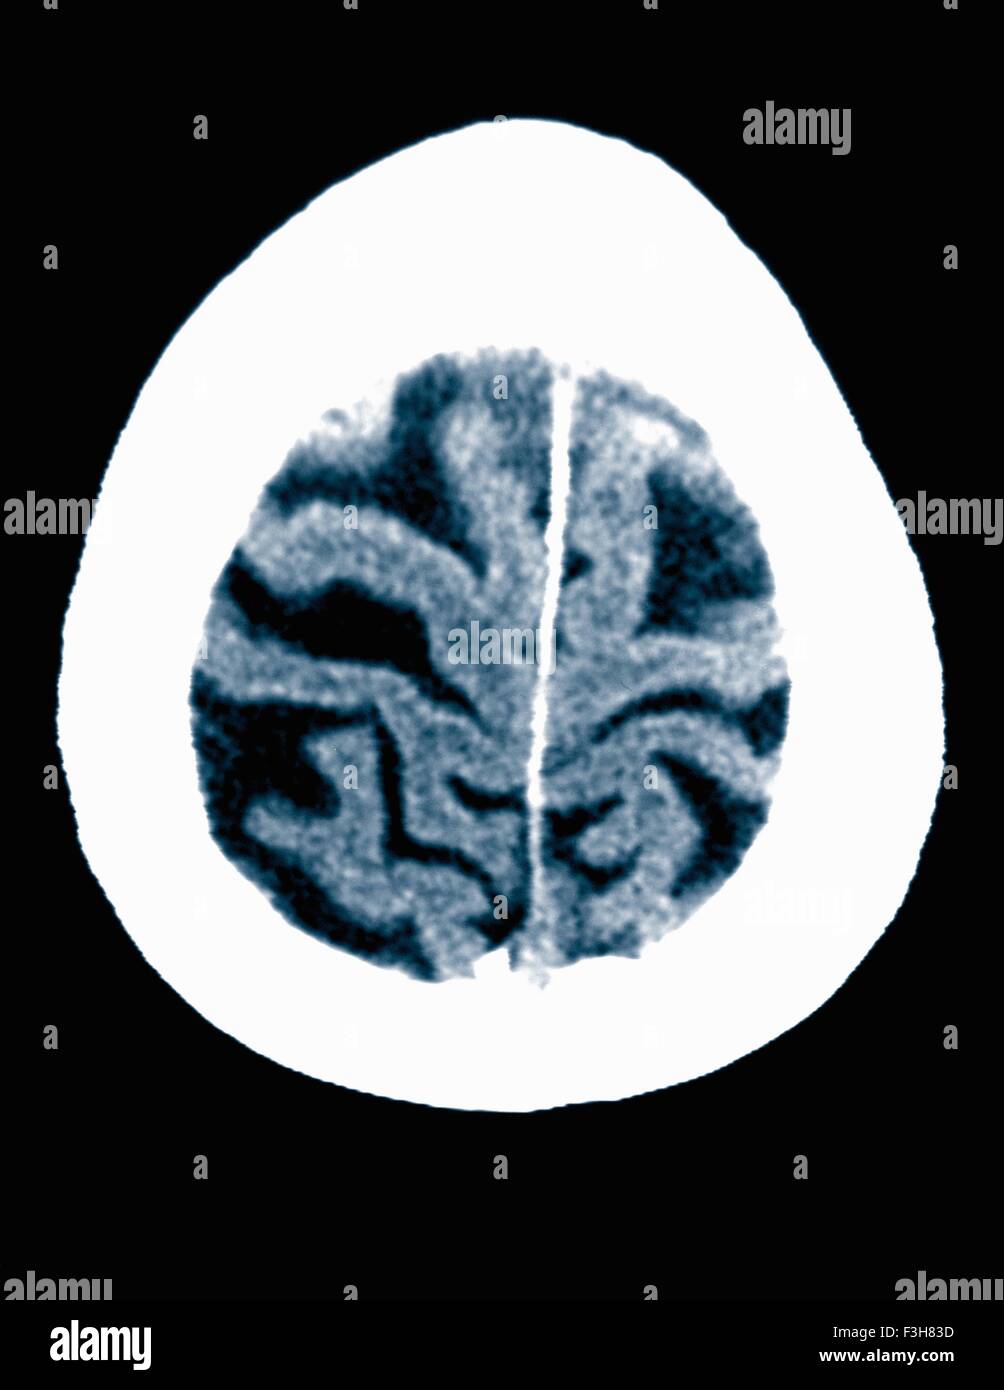

From www.alamy.com

CT scan 84 year old male with Alzheimer's disease. CT shows brain Will A Ct Scan Show Alzheimer S Web brain scans also can identify changes in the brain's structure and function that suggest alzheimer's disease. First, the scan helps your doctor rule out conditions. Web a pet/ct scan can help differentiate alzheimer's disease from other types of dementia. Web ct scans are the most common type of brain scan used in dementia diagnosis. Web doctors can use mri. Will A Ct Scan Show Alzheimer S.

CT scan 84 year old male with Alzheimer's disease. CT shows brain Will A Ct Scan Show Alzheimer S Web doctors can use mri or ct scans to help diagnose dementia or even detect signs of dementia before. Web the goal of a head ct scan for alzheimer’s disease is twofold. Web while they may show shrinkage of some brain regions associated with alzheimer's disease, mri scans also rule out other conditions. First, the scan helps your doctor rule. Will A Ct Scan Show Alzheimer S.